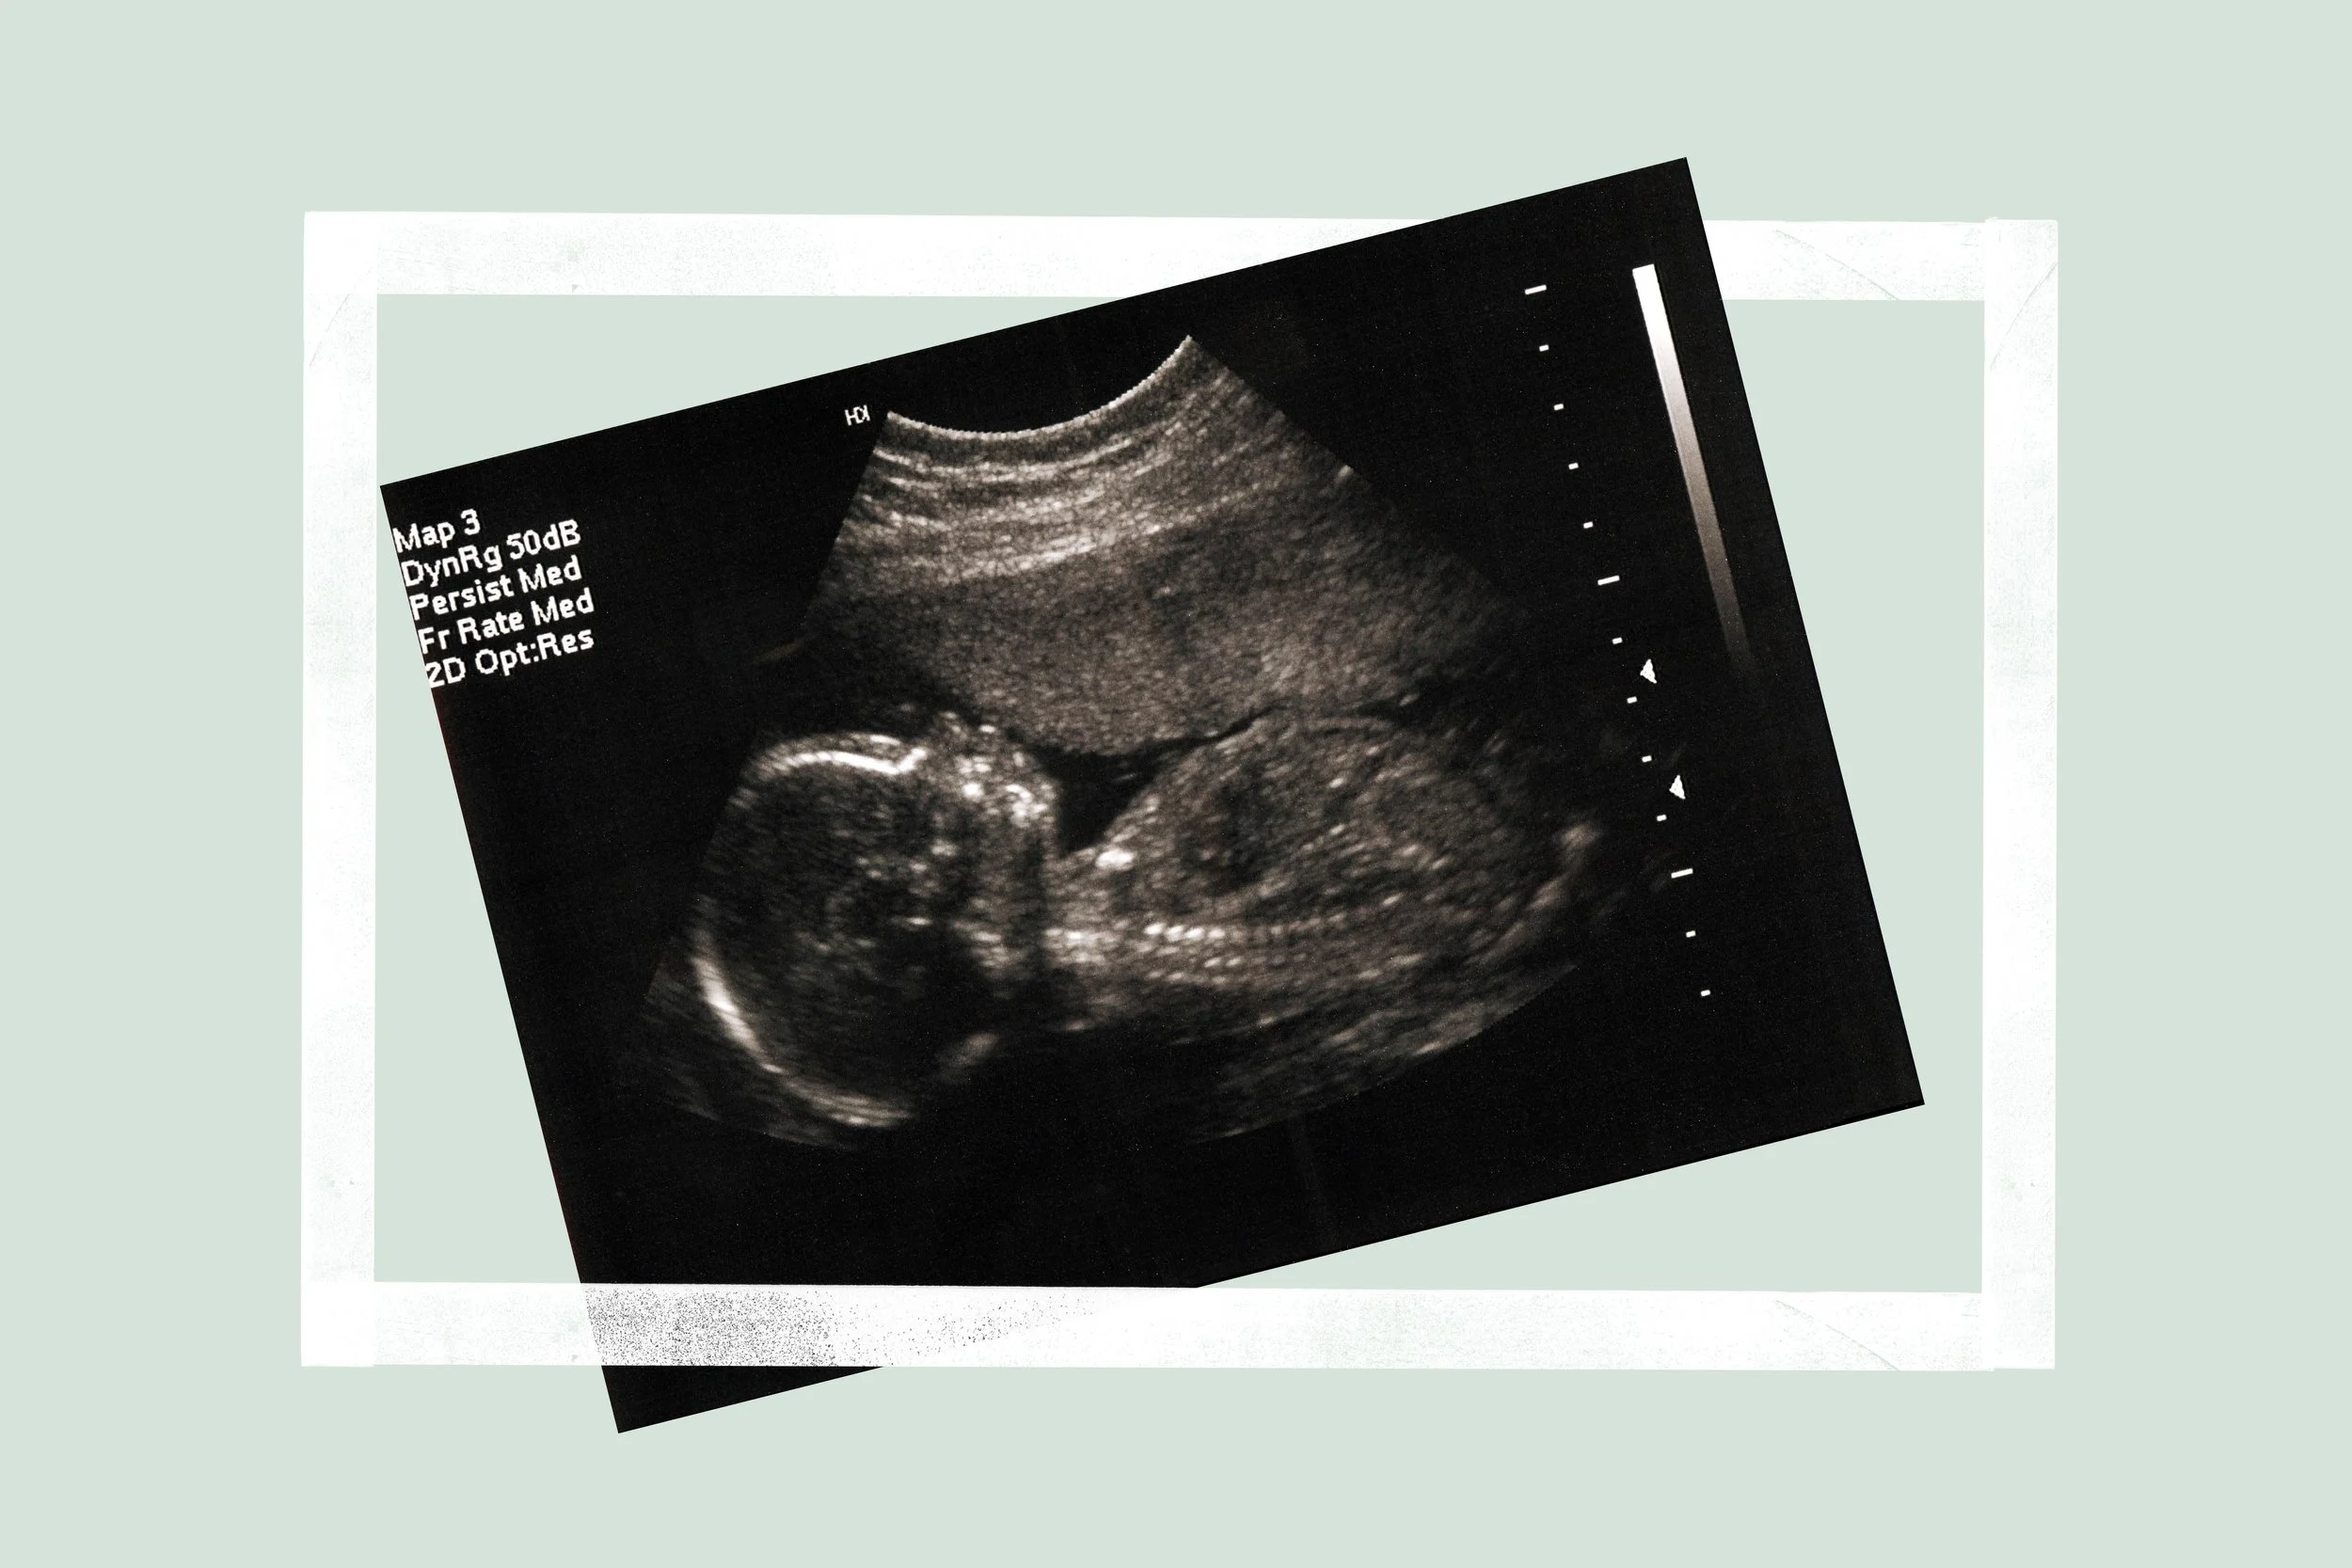

Preparing for the 20 week scan

You’ve almost reached the halfway mark and in the next week or so you’re going to have the opportunity to see your baby again!

The 20-week scan is a detailed scan of your baby’s physical development - it looks at your baby's bones, heart, brain, spinal cord, face, kidneys and abdomen. It also looks at the placenta, blood flow and fluid surrounding your baby.

The person performing the scan will also check your baby’s genitals so this is the chance to find out the sex of you baby if you haven’t already and would like to.

The length of your baby as well as their head and tummy circumference will also be plotted on a graph to monitor how they are growing.

The 20-week scan screens for a number of rare conditions and that is why it is also known as the anatomy or anomaly scan. You will be told at the end of the scan if any further follow up is recommended.

You’ll be given more photos of your baby and you can then compare them to the 12-week ones and see how much they’ve changed and grown!